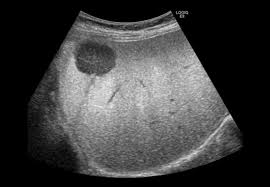

Cirrhosis and a liver lesion on screening ultrasound raises concerns for this complication.

What is Hepatocellular Carcinoma (HCC)?